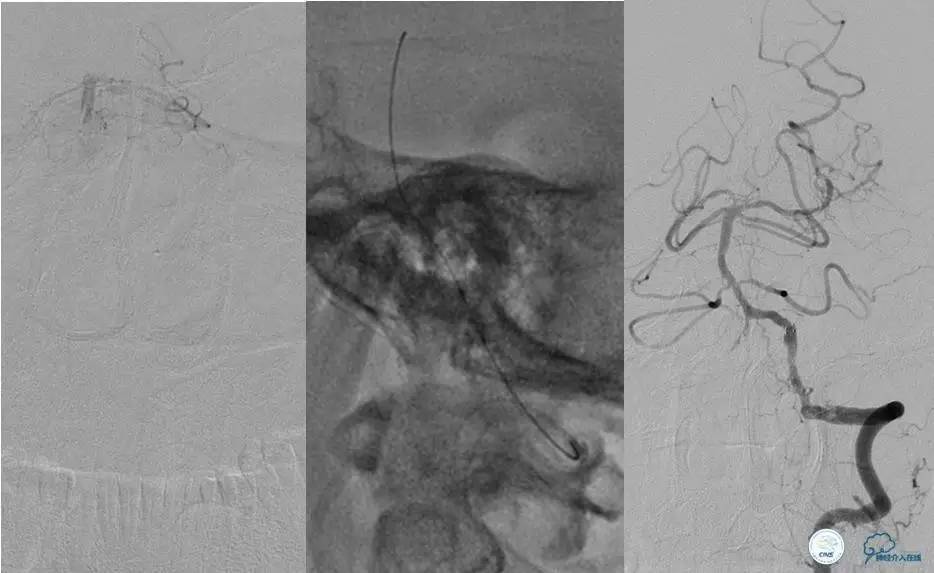

造影评价血管、判断闭塞段,微导丝小心穿过闭塞段,微导管造影,交换技术,球囊扩张,Enterprise支架。在后扩张时导丝刺破M3段血管,蛛网膜下腔出血(SAH)。

微导管进入破裂血管,栓塞弹簧圈1枚,出血停止,结束手术。继续双抗,术后2天肌力2级,神经功能恢复明显加快。

术后即刻和6天后CT,患者无明显临床症状。

半年后复查造影,无支架内再狭窄,可见弹簧圈,患者恢复至自己柱杖行走。